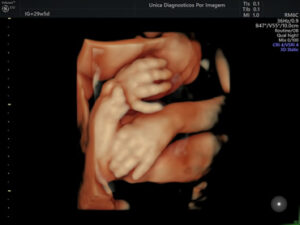

Exame importante que tem como objetivo avaliar a anatomia do feto e detectar possíveis malformações. Deve ser realizado preferencialmente realizado